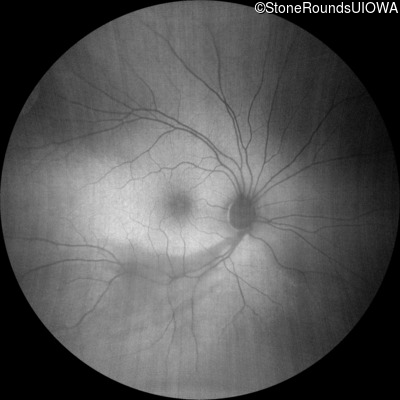

Age at visit: 7 years

OD OS

This 7 year old boy failed a vision screening test at his pediatrician 5 months ago.

Age at visit: 9 years

Age at visit: 11 years